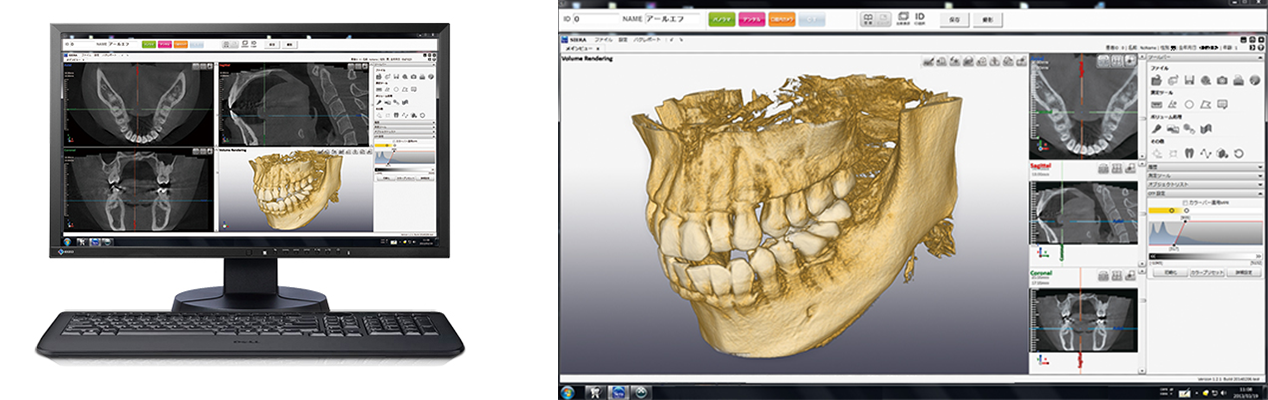

歯科用3D(立体)デジタルCT

従来のレントゲンでは見えなかった事、分からなかった事が、歯科用CT撮影なら正確に把握することができ、患者さんの安全性と根管治療や親知らずの抜歯、インプラント治療のクオリティーを高めることが可能となります。

従来のレントゲンは平面のみの情報でしたが、歯科用CTを用いることで3D(立体)の情報が得られ、立体的な骨の形態、歯根の形態、神経の位置までもが分かるため、より精度の高い診断・安全な治療を行うことができます。

さらに、医科用と比べて局所的な歯科用レントゲンはX線量が少なく、低被曝で身体にもやさしい設備です。

インプラント治療などにも活躍

インプラントの術前立体シミュレーションや、歯周病での骨の診査、歯根の病巣や破折の状態、埋まっている親知らずの診査など、多岐にわたる高度治療に貢献します。